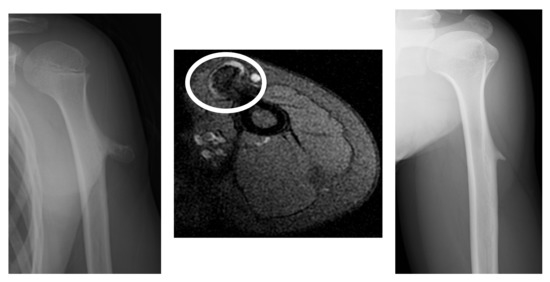

3.1.1. Case 1

3.1.2. Case 2